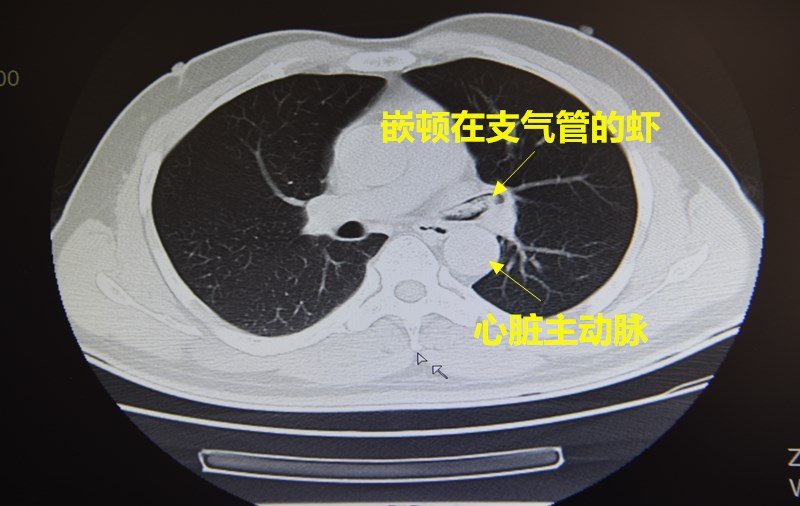

一整夜过去,张先生始终胸闷不适,还咳出了些许血丝,意识到问题的严重性,这才火急火燎赶往医院。医生为张先生紧急安排CT 检查,通过初步检查判断,一只虾嵌顿在了左下肺叶的支气管里,需要支气管镜手术才能取出。

想从支气管内取出一整只虾并非轻而易举,万一虾壳断裂落入肺部深处,支气管镜便难以取出,支气管又与心脏主动脉相邻,如果操作不当,虾坚硬的外壳划伤、刺破气管甚至主动脉,后果更不堪设想。